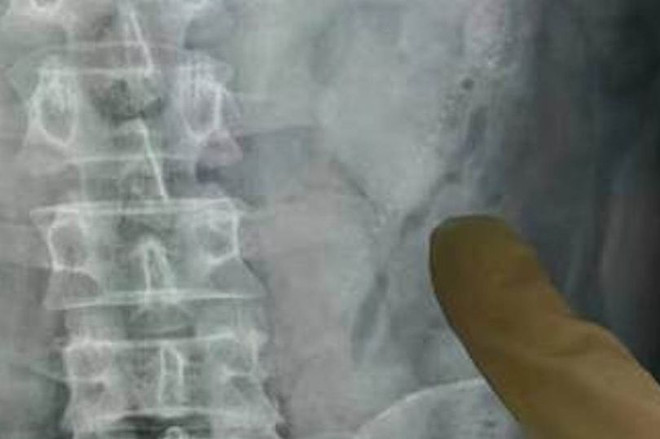

Suýt mất mạng vì nhét 2 con lươn vào hậu môn khi say xỉn ảnh 1Bác sỹ chụp x-quang để xác định vị trí hai con lươn. (Nguồn: mirror.co.uk)

Bác sỹ đã phải chụp X-quang vùng bụng để xác định vị trí của hai con lươn. Họ thấy rằng một con lươn đã chui vào phần trên của ổ bụng: “Con lươn này dài hơn 10cm và dày 2cm. Nạn nhân có thể đã mất mạng nếu nó trườn xa hơn và tiếp xúc với các bộ phận nội tạng.”